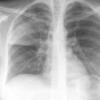

Round pneumonia

different case